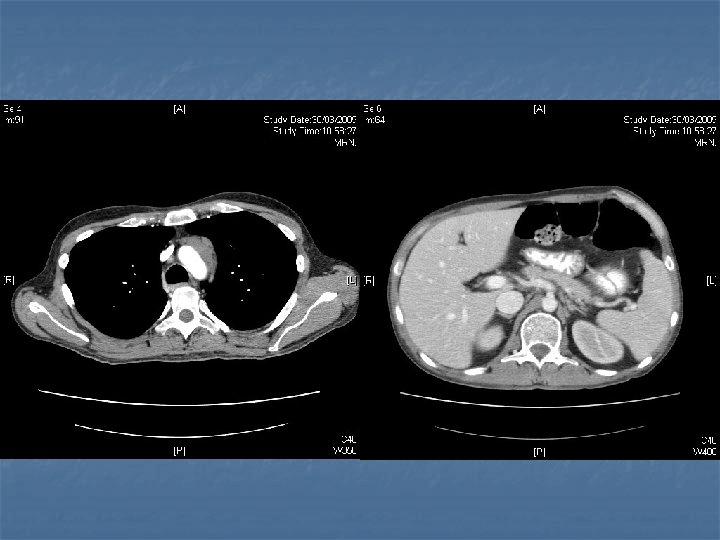

n n n PRETREATMENT INVESTIGATIONS: FBC, Renal and liver function, LDH, urate, Ig. GS. Histology review. Marrow aspirate+trephine (cytogenetics, immunology) CD 4 , HIV viral load. CT Scans. (MR Brain) (PET scan ) Echo / LVEF CMV, Hep B+C, Toxoplasma serology MAI screen. LP for CSF cytology +/- intrathecal Rx. (DLBC , Burkitt, Plasmablastic).